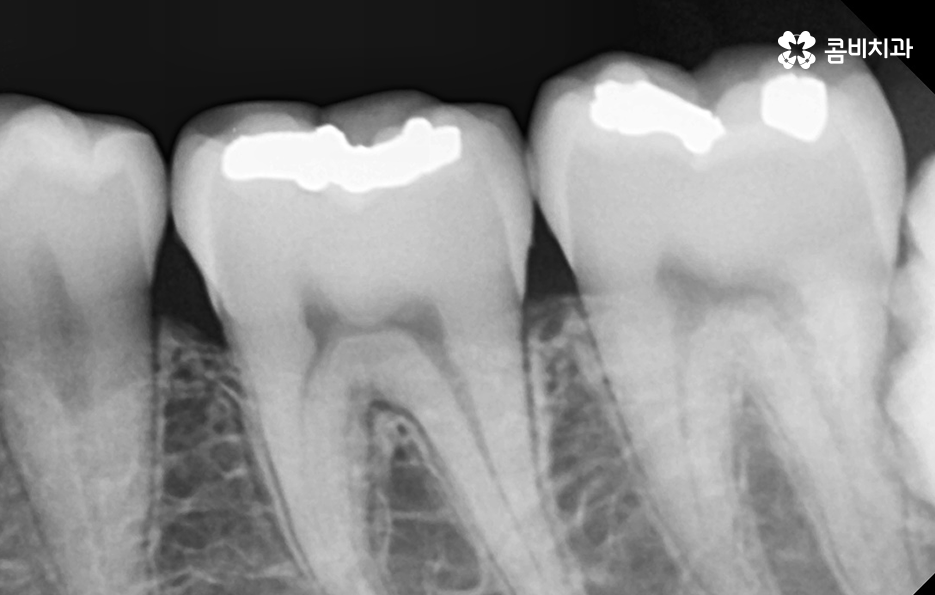

출처 아카이브 열기흔히 이가 썩었다고 표현하는 충치는 흔히 3단계로 구분하고 있는데요. 치아의 구조를 법랑질, 상아질, 치수로 구분할 때 치아의 겉부분인 법랑질의 충치를 1단계로 보고 법랑질 안의 상아질까지 충치가 진행된 경우 2단계로 보고 있어요

보통 충치로 인해 치아에 자극을 느끼고 시림을 느끼는 단계가 충치 2단계인 상아질 충치에 해당되고 있으며 치아의 구조로 볼 때 법랑질에 비해 상아질이 좀더 약하기 때문에 상아질까지 충치가 진행되면 상아질에 느껴지는 자극이 치수에 빠르게 전달되어 시림 증상을 쉽게 느끼는 경우가 많을 거예요

많은 분들이 오래된 보철물로 인해서 2차 충치의 문제가 발생되고 있으며 보철물 안에서 발생한 2차 충치의 경우 눈으로 확인이 어렵다는 점에서 아플 때까지 참다가 치료 시점을 놓치는 경우도 많을 거예요

오늘 소개드린 환자분의 케이스는 사랑니 만의 문제라고 보긴 어렵고 오래된 보철물로 인한 2차 충치로 볼 수 있으며 새로운 보철물로 어금니 충치치료 다시 해야하는 케이스로 볼 수 있는데요

이번 케이스는 나이가 들수록 겪기 쉬운 복합적인 치아 문제의 예시를 좀더 이해하기 쉽게 알려드릴 수 있을 것으로 보여서 케이스 사진을 준비 했으며 이러한 복합적인 치아 문제를 예방하고 조기 치료하기 위해서는 주기적인 검진이 정답이라고 말씀드리고 있어요

오늘 케이스 사진의 경우 사실상 사랑니 하나만 보더라도 주변 치아에 충치 및 치주질환을 일으키기 쉬운 사례이며 누운 사랑니로 인해서 어금니의 씹는면 만이 아니라 인접면 충치나 손상으로 이어지기 사례로도 볼 수 있는데요